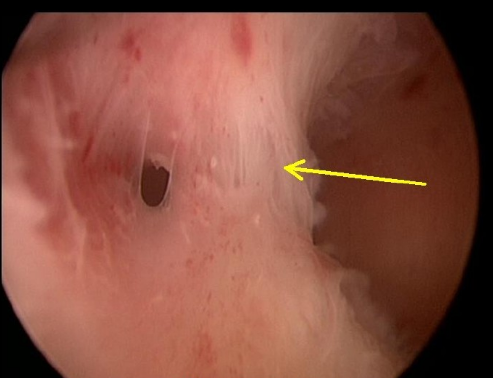

5,宫腔镜手术是诊断宫腔黏连的金标准.

图片尺寸493x378

宫腔黏连是什么样的?